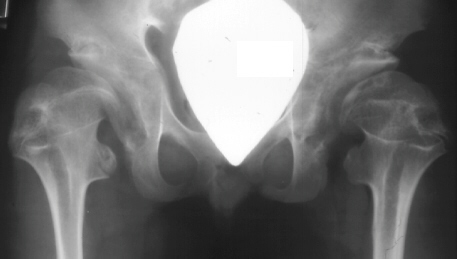

SPONDYLO-EPI-METAPHYSEAL DYSPLASIA WITH JOINT LAXITY (SEMDJL)

Radiographic features: